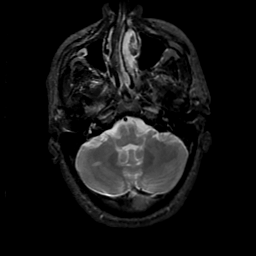

MR Study #18, July 21, 1991 -- Slice #10